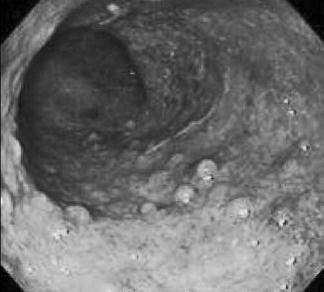

При лабораторном исследовании может быть обнаружена анемия (при кровотечении и лейкоцитоз (при воспалении). В основном диагноз устанавливается на основании клинических, рентгенологических и эндоскопических данных. При эндоскопии выявляется отек слизистой, гиперемия, обеднение сосудистого рисунка, контактная кровоточивость, эрозии, налет фибрина, псевдополипы и грануляции (рис. 178).

Рис. 178. Эндоскопическая картина при язвенном колите